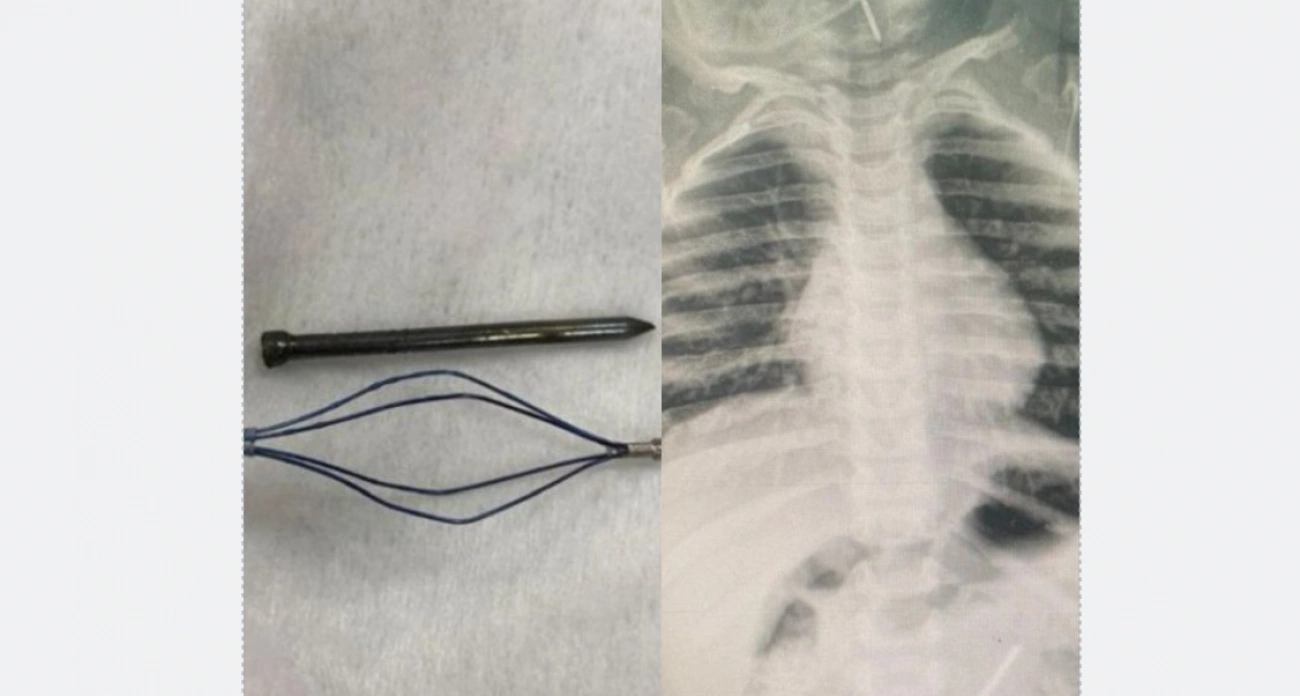

За последний месяц было несколько сложных случаев. Двухлетний мальчик, оставшись без присмотра взрослых, проглотил два гвоздя, один из которых врачи достали из горла, а второй – из кишечника. Он поступил по линии скорой предположительно через два часа. Подросток 14 лет поступил с тяжелым состоянием после того, как поперхнулся кнопкой, которая застряла в бронхе. Восьмилетняя девочка после потери молочного зуба поперхнулась им, и врачи удалили зуб из дыхательных путей через 10 часов после происшествия.